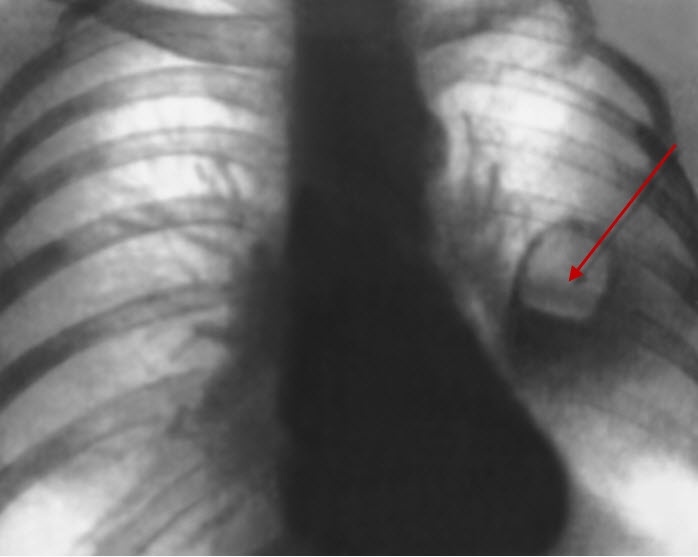

Патологічний процес викликається специфічними збудниками, які проникають в легені через бронхи. Це можуть бути аеробні бактерії грамнегативною ряду, анаеробні мікроорганізми, золотистий стафілокок , стрептокок і ін. Яка збільшує фактором виступають запальні захворювання в носоглотці і порожнини рота, такі як гінгівіт , пародонтоз , а також тонзиліт . Абсцесс легочной ткани Абсцес легеневої тканини може виникнути в результаті проникнення блювотних мас в порожнину бронхів, що часто відбувається при сильному алкогольному сп'янінні, під час наркозу. Також аспірація може наступити в результаті попадання в дихальні шляхи і бронхи чужорідних тіл . У деяких випадках вогнище інфекції утворюється в результаті патології легеневих капілярів. Цей варіант характеризується швидко розвиваються сепсисом. Також небезпечний інфаркт легкого, спровокований емболією. Даний процес призводить до вторинного бронхогенного інфікування і розвитку абсцесу. Причиною абсцесу можуть стати травматичні ушкодження, ножові і вогнепальні поранення грудної клітини.

analiz-volos Для діагностування абсцесу легкого проводять аналіз крові на лейкоцитоз, анемію, а також гипоальбуминемию. Показано мікроскопічне дослідження мокротиння з метою виявлення бактерій-збудників або нейтрофілів. Також береться на дослідження плевральна рідина.